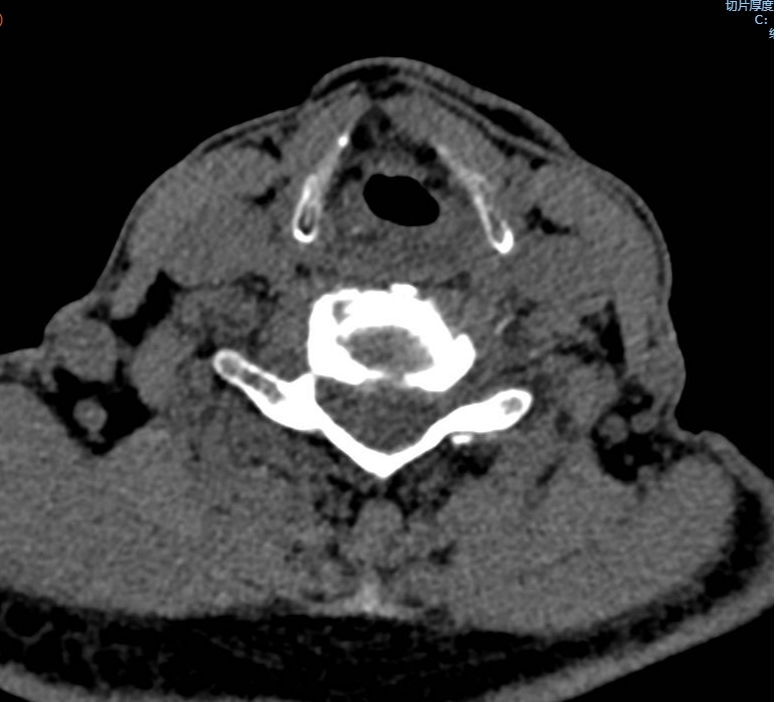

手術(shù)之后3天,黃大伯疼痛得到很好緩解,露出了許久沒有的笑容,終于可以安心躺著睡覺了,1個(gè)月后基本恢復(fù)了正常生活,6個(gè)月后復(fù)查CT發(fā)現(xiàn)突出的頸椎間盤已經(jīng)基本消失了,黃大伯一家人對(duì)治療效果非常滿意。

手術(shù)之前CT,巨大突出物 術(shù)后6個(gè)月復(fù)查CT:突出物消失